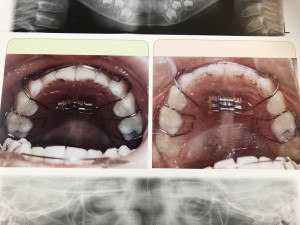

当院では本格矯正と言って直接歯に装置を着けて歯列を治していくものがあります。

歯を積極的に動かせるのはこちらになります!(個人差があります)

歯列が気になるお子様や大人の方もこちらの矯正ができます。

そして、お子様向けで早めに歯列を綺麗に並ばせたい方には床矯正という物もやっています。

こちらは取り外しができる物になります。